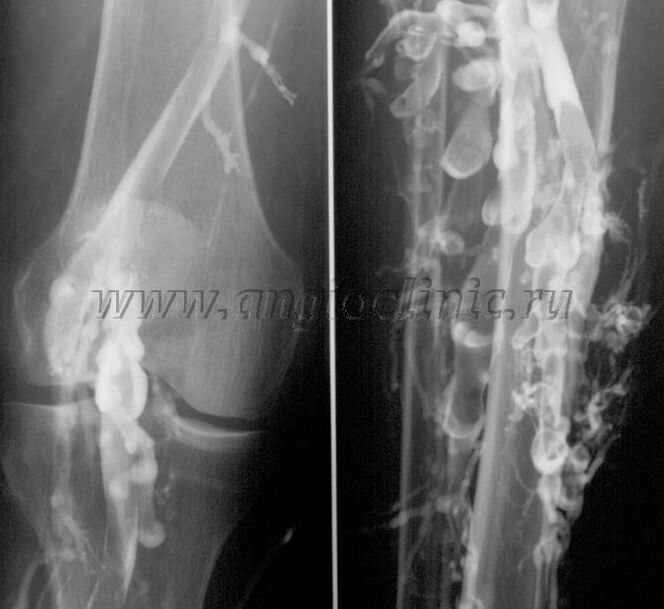

ونوگرافی کنتراست

معمولاً اسکن اولتراسوند برای تشخیص کامل پاتولوژی وریدی کافی است، اما در برخی موارد بررسی رابطه بین وضعیت سیستم وریدی عمقی و سطحی به ویژه در موارد عود رگهای واریسی و وریدهای واریسی ثانویه ضروری است.

اسکن سونوگرافی

برای حل این مشکلات از معاینه اشعه ایکس حاجب استفاده می شود. ورید صافن سوراخ می شود و ماده حاجب تجویز می شود. حرکت کنتراست بر روی مانیتور دستگاه اشعه ایکس مشاهده می شود و تمام آزمایشات و برون ریزی های لازم انجام می شود. در حال حاضر، ونوگرافی برای وریدهای واریسی بسیار نادر استفاده می شود.